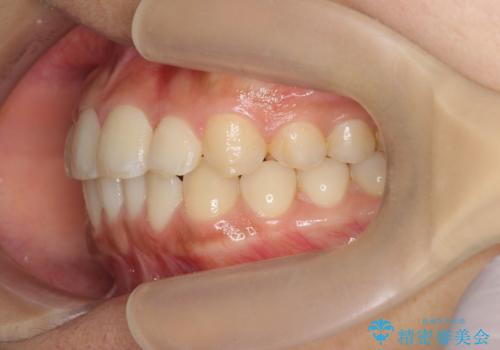

- 前歯のガタつき、上下たがい違いになっている歯並び(クロスバイト)の改善を求めて来院されました。

インビザラインによる矯正治療を行いますが、クロスバイトの改善をワイヤー部分矯正で事前に行うことにより治療期間の短縮する治療計画を立案します。